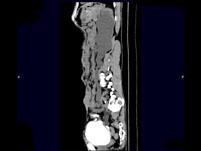

问题 男,55岁,尿频,尿痛伴低热乏力1月。如图所示,下列说法正确的是 ( )

选项 A.左侧输尿管多发性狭窄 B.右侧肾积水 C.膀胱变形 D.左侧输尿管结核 E.左侧输尿管癌

答案 ABCD